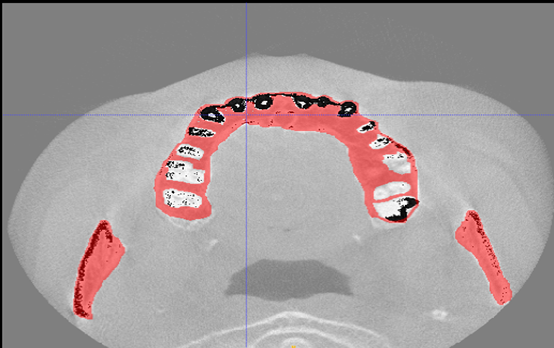

工作室团队成员目前包括李思博士、何远清老师、胡晨恺医生(南昌大学第二附属医院心内科主治医师)。另现有7名员工成员,包括20级1名、21级1名、22级5名,员工成员目前的研究主题包括:基于深度学习的冠脉造影狭窄智能检测技术研究(如图1所示);基于神经网络的智慧城市停车位检测技术研究(如图2所示);基于深度学习的口腔CT牙槽骨分割技术研究等(如图3所示)。

图3:基于深度学习的口腔CT牙槽骨分割技术研究